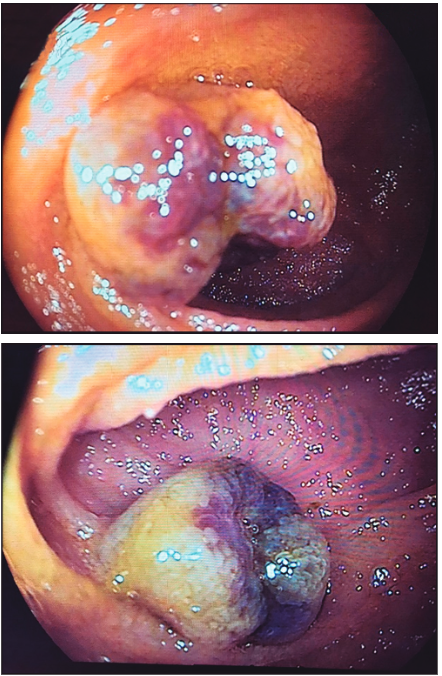

A los seis meses del tratamiento, intercurrió con un nuevo episodio de anemia sintomática. Se realizó enteroscopía anterógrada con doble balón (Fujinon® serie EN-450T5), sin evidencia de lesiones, con marcación del sitio de máxima inserción y enteroscopía retrógrada, evidenciandose en ileon, proximal a la cicatriz del tratamiento previo (Figura 2) una lesión similar a la anterior (Figura 3), de 25 mm de diámetro. Se realizó escleroterapia con polidocanol al 1% (seis mililitros), sin complicaciones.

Figura 3. Lesión elevada, lobulada de 20 mm de diámetro, de color azulada, compatible con

hemangioma, evidenciada por estereoscopía retrógrada asistida por dispositivo doble balón.